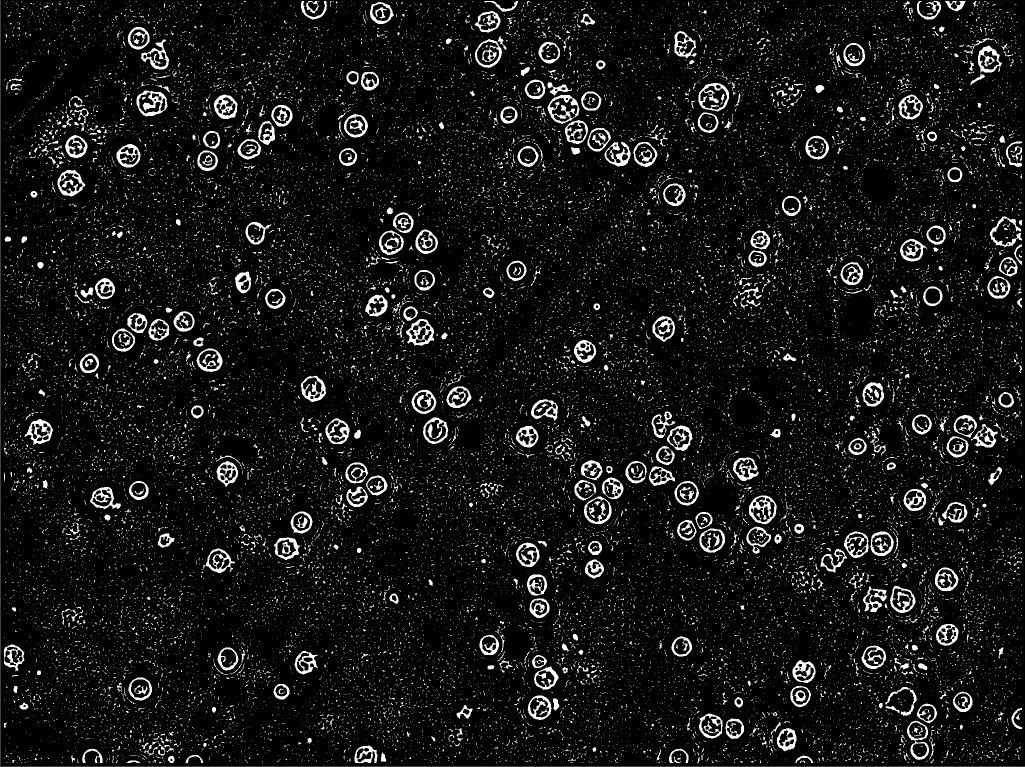

해당 프로젝트의 이미지분작 시작은 필요없는 부분을 제외시키는 것으로 시작하였습니다. 색상이나 외각선을 기준으로 필요없는 부분은 빠르게 뽑아내서 제거하고 ! 기준이 애매한 외각같은 경우는 흐리게 만들거나, 여러 기법을 통해서 노이즈를 제거하여 원하는 오브젝트를 추출 하는 것으로 시작합니다.

해당 이미지는 노이즈 제거중인 이미지이다.

오브젝트 외각선을 추출한 이미지